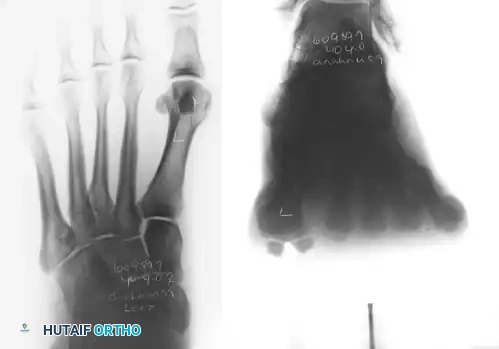

The oblique view is critical for profiling the fibular sesamoid.

FIGURE 81-100 B: Oblique view profiles the fibular sesamoid. Note the cystic fibular sesamoid on the right foot. This probably represents an old fracture through the syndesmotic union of a bipartite sesamoid.